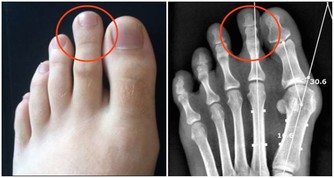

心腦血管疾病患者由於血管壁彈性降低,流向大腦的血液量減少,導致大腦缺血缺氧。當大腦缺血缺氧時,人就會哈欠連連,因為打哈欠能使腦細胞的供血供氧能力得到暫時的改善。而長期高血壓等心腦血管患者,由於動脈硬化程度較高,全身血管彈性變差,特別是一些小血管壁越來越薄,甚至個別地方產生「鼓包」(即微小的動脈瘤)現象,一旦血壓驟然升高,容易導致腦血管管壁破裂,形成出血性腦卒中。高血壓可使腦血管動脈硬化的發展加速、加重,血管硬化造成的血管狹窄和硬化的血管壁內形成的斑塊破裂,引起的血栓則會造成血管的堵塞,從而引發缺血性卒中。